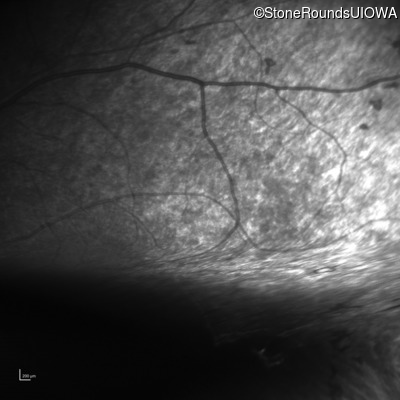

Infrared Fundus Photograph - Right - No Light Perception

Exemplar